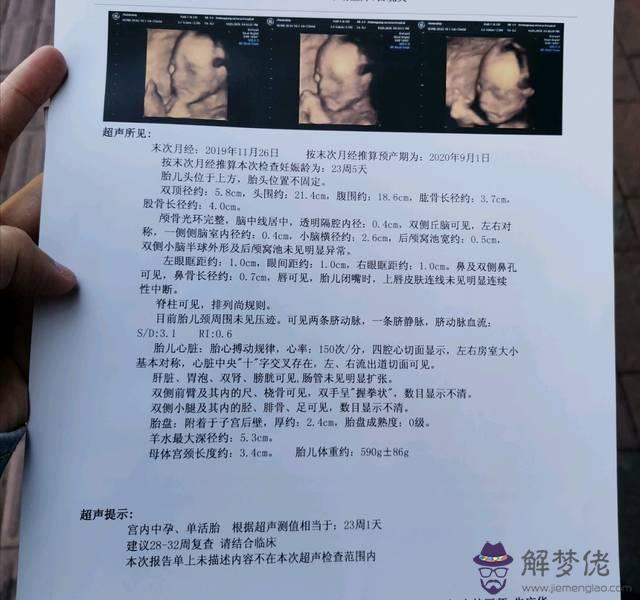

5、懷孕多久可以看出性別:怎樣從四維彩超的報告單的數據看出是男孩還是女孩?

四維彩超主要是用于檢查胎兒發育情況的輔助項目,通過此項檢查,可以了解胎兒在母體內各部位發育情況,如胎位,頭面部、臟器。神管、以及四肢發育情況,這個檢查項目多數在懷孕26-30周期間做。

6、懷孕多久可以看出性別:四維彩超單怎麼看是男孩還是女孩?

四維彩超主要是用來檢查胎兒發育是否正常,排除胎兒發育畸形的檢查項目。首先四維彩超主要檢查的是面部畸形,四維彩超檢查時會重點觀察胎兒雙眼與眼眶是否等大等圓以及眼距的測量。再就是可以詳細觀察軟腭以及硬腭,上唇弧型曲線是否連續